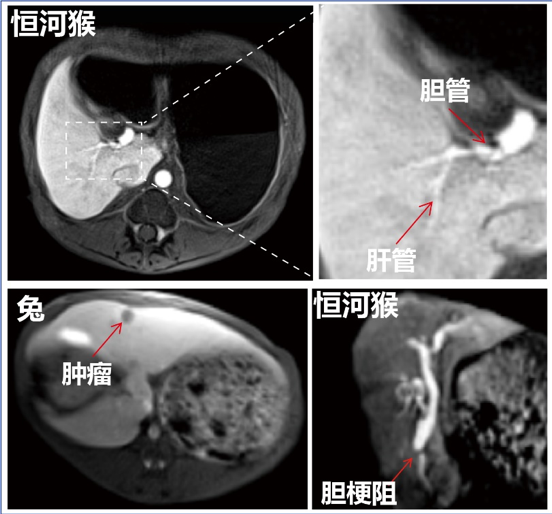

研究结果表明,MnFe2O4纳米颗粒表面的Mn离子和其表面修饰的乙氧苯(EOB)配体可实现对肝细胞SLC39A14和OATP1的双靶点协同靶向作用,显著提升了特异性和亲和力,活体(猪)实验显示其肝细胞特异性分布可高达70.59%。猴、猪等大动物实验肝胆成像结果显示,与临床Gd-EOB-DTPA相比,可使肝对比度增强5.8倍,并可高清晰分辨0.5毫米的肝管。同时肝实质和胆管显像速度也提升了2倍以上,显著减少患者检测时间,提高了检查效率。活体肝癌成像结果显示,该对比剂可将微小肝癌病灶(<0.5厘米)的检出率人48%提高至92%,并可清晰判断胆梗阻位置与梗阻程度,有望用手无创胆管成像。初步非临床GLP评价和大动物安全性评价结果均显示出良好的安全性,可通过肝、肾快速清除,7天残留率小于1%,具有极好的临床转化潜力。该研究双靶点设计的新型肝细胞特异性准顺磁纳米对比剂为肝癌早期发现提供了 新的影像诊断工具。MnFe2O4-EOB-PEG已注册商标“玵立显”,目前在西安超磁科技进行临床转化研发。

MnFe2O4-EOB-PEG纳米对比剂磁共振肝胆成像